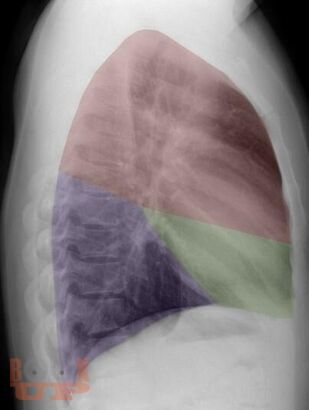

Рентгеноанатомия органов грудной клетки

В учебном пособии представлена информация о нормальной рентгеновской анатомии органов грудной полости, вариантной анатомии, наиболее частых аномалиях развития, скиалогии, алгоритме описания рентгенограмм и основных требованиях по оформлению протокола рентгенологического исследования.